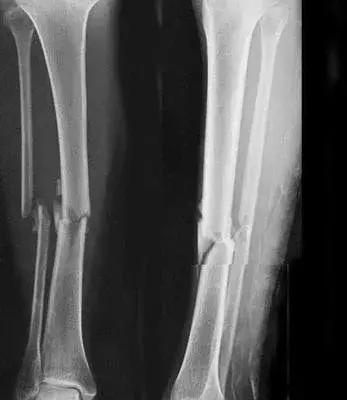

5、小腿踢球时骨折过,还能当兵吗?

四肢单纯性骨折,治愈1年后,X线片显示骨折线消失,复位良好, 无功能障碍及后遗症(空降兵除外),合格。